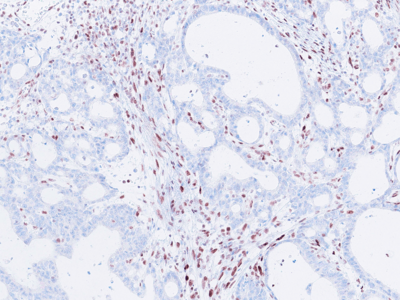

Histologically, the tumour was confirmed to be an adenocarcinoma invading through the gastric submucosa into the muscularis propria (Panel A), showing multiple architectural patterns. While the majority of the lesion displayed a tubular and papillary arrangement of neoplastic cells (Panel B), there were also mucin pools containing floating tumour cells (Panel C), as well as areas of discohesive signet-ring cells (Panel D), so called for their intracytoplasmic mucin droplet that eccentrically displaces the nucleus. The different architectural patterns were not entirely independent of each other nor were they intermingled, but rather arranged side by side (Panel E).

Immunohistochemical analysis of mismatch repair proteins demonstrated loss of MLH1 (Panel F) and PMS2 expression. MSH2 and MSH6 expression were retained.